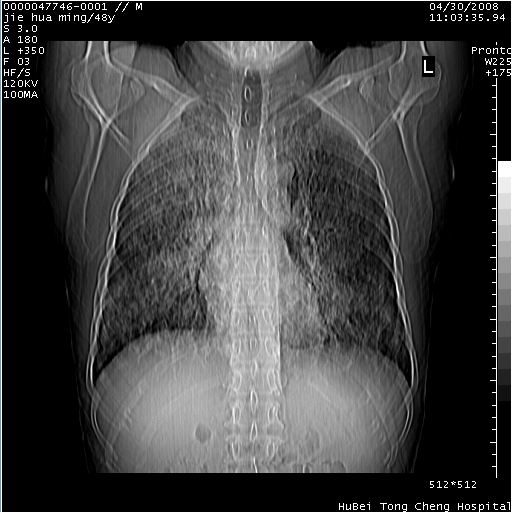

以下是引用dr.yang在2008-5-1 6:25:00的发言:[br]两肺广泛毛玻璃样的片状影,密度不均,边缘欠清,呈碎石路样改变,[br]考虑,1双肺间质性肺炎,2肺泡蛋白沉积症3支气管肺泡癌[br]

以下是引用zsl6918在2008-5-1 7:35:00的发言:[br]双肺磨玻璃样病变,可见铺碎路石征,病变区与正常区交错。边界清晰。符合肺泡蛋白质沉着征,高分辨扫描会更清楚漂亮。建议临床肺泡灌洗。

以下是引用yangyudong333在2008-5-1 5:36:00的发言:[br][br] 两肺广泛毛玻璃样的片状影,密度不均,边缘欠清,呈碎石路样改变,[br]考虑,1双肺间质性肺炎,2肺泡蛋白沉积症[br]